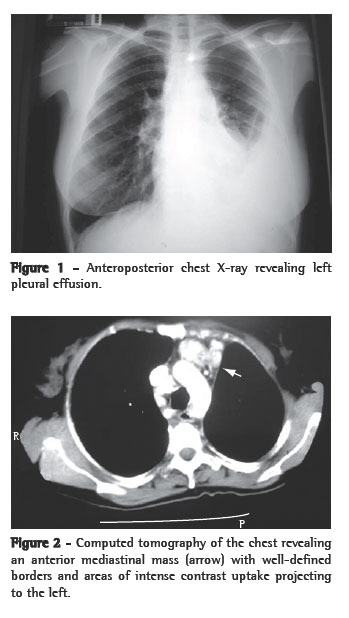

A 45-year-old female patient (married and a dressmaker) without respiratory symptoms was admitted to undergo stapedectomy due to otosclerosis (she had a 4-year history of buzzing in the ears and bilateral conductive hearing loss). The surgery was postponed due to the incidental finding of left pleural effusion on a preoperative chest X-ray (Figure 1).

The physical examination revealed that the patient presented good general health status (lymph nodes were not palpable). The left inferoposterior third of the chest was rigid, with absent breath sounds upon auscultation. Pleural fluid testing (thoracocentesis) revealed the following: 25% neutrophils; 70% lymphocytes; 5% macrophages; few erythrocytes; absence of neoplastic cells; glucose, 102 mg/dL; total proteins, 5.5 g/dL; lactate dehydrogenase, 264 U/L; and pH, 7.45. No acid-fast bacilli were found in the direct examination of the pleural fluid, and a culture was negative for Mycobacterium ­tuberculosis. A pleural biopsy revealed chronic nonspecific pleuritis with mild fibrosis. The induration diameter on the purified protein derivative skin test was 30 mm, and the serology was negative for HIV-1 and HIV-2. In view of the diagnosis of probable pleural tuberculosis, treatment with regimen I (rifampicin, isoniazid, and pyrazinamide) was instituted. After 6 months of treatment, there was no resolution of the left pleural effusion volume, although the patient remained free of respiratory complaints. Computed tomography of the chest revealed a left anterior mediastinal mass with well-defined borders near the heart, with areas of intense contrast uptake (Figure 2), in addition to the left pleural effusion.